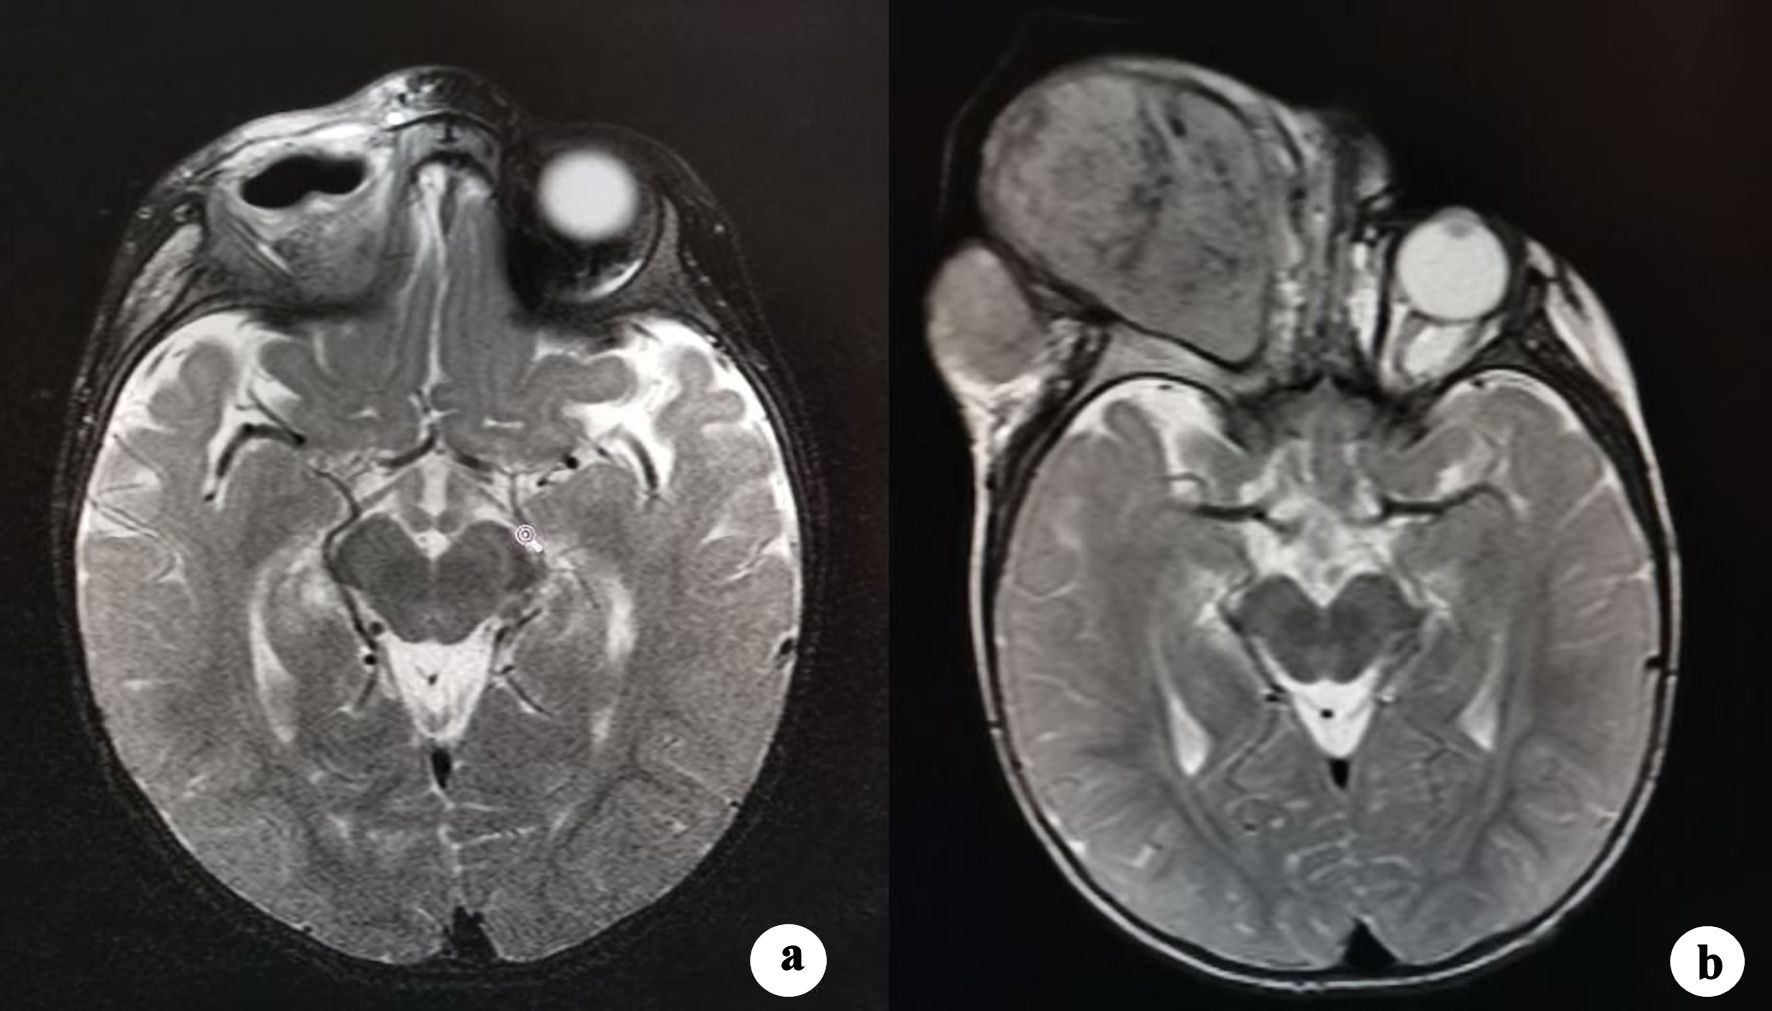

The patient underwent mass removal and orbital exenteration. Surgery was performed under general anesthesia and consisted in complete removal of the mass and the entire content of the orbit including both inferior and superior eyelids. It was possible to appreciate a lesion of considerable dimensions (Fig. 2a, b), whose weight was 506 g and dimensions were 12 × 9 × 5 cm. The mass had encephaloid color and consistence and contained suppurative and necrotic tissue, surprisingly hosting worms (Fig. 2c). Histopathological examination showed an undifferentiated retinoblastoma (Fig. 2d), massively infiltrating extrinsic muscles, lacrimal gland, skin and optic nerve stump. The child underwent head and orbit magnetic resonance imaging (MRI) after surgery. As shown in Figure 3a, there was no evidence of tumor residues in the anophthalmic cavity nor invasion in the adjacent structures. Bone scintigraphy, lumbar puncture and bone marrow aspiration were performed, which resulted negative. After orbital exenteration, systemic chemotherapy and radiotherapy were started following the ICE protocol, which involves the combination of ifosfamide, carboplatin and etoposide. Ifosfamide was given at a dose of 2 g/m2 in 4-h infusion on days 1, 2, and 3 (for a total dose of 6 g/m2), associated with Uromitexan and hyperhydration. Uromitexan 700 mg/m2 was given intravenously for 30 min before ifosfamide, and at 2,000 mg/m2 in the following 24 h, together with hyperhydration with 5% glucose solution of 2,000 mL/m2 in 24 h. Etoposide was administered at a dose of 100 mg/m2, diluted in 5% glucose solution to the maximum concentration of 0.4 mg/mL. The divided dose was administered intravenously over 1 h on days 1, 2, and 3. Carboplatin at a dose of 600 mg/m2, diluted in 200 mL/m2 of 5% glucose solution and infused intravenously slowly over 2 h is administered on day 3.

![]() Click for large image | Figure 3. (a) Postoperative T2-weighted MRI scan shows right orbital cavity free from lesions with intact adjacent soft tissues and bones. (b) T2-weighted MRI scan obtained 1 month after the start of the therapy. An amount of effusive isointense tissue has developed in the right orbital cavity, causing its deformation. MRI: magnetic resonance imaging. |

Unfortunately, 2 months after the start of therapy, the disease recurred in the orbital cavity. As documented by MRI (Fig. 3b), there was a complete filling of the orbital cavity by the tumor recurrence, with external bulging and extensive infiltration of the surrounding bone structures and soft tissues, with particular interest of the preauricular region.